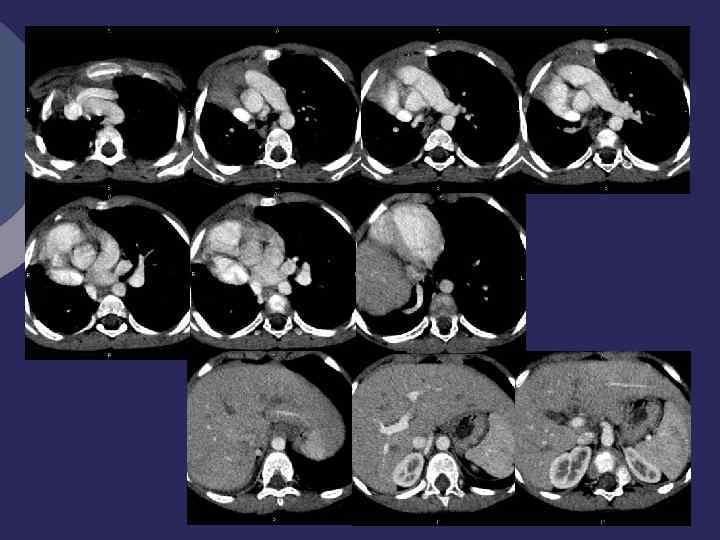

Легочная секвестрация (Pryce, 1946). Ø Порок развития, характеризующийся наличием участка легочной ткани, расположенного внутри легкого или вне его, не связанного с бронхиальной системой легкого, содержащего элементы бронхиальной и альвеолярной ткани Ø Кровоснабжение - аномальная артерия, отходящей от Ао или ее ветвей Ø Отток - в непарную или полую вену Ø 3 -6 неделя эмбриогенеза Ø 1% оперированных по поводу хроничес- ких нагноений легких

Внутрилегочная Внелегочная секвестрация Ø аномальный участок расположен Ø аберрантное легкое, доля, имеет внутри легочной ткани, висцеральную плевру Ø не имеет плеврального отграничения Ø может располагаться как внутри легкого, так и вне его. Ø Морфологически – плотный желтоватый пигментированный участок с одной или несколькими кистами. Ø Клиника – хронического нагноительного процесса. Внутридолевая Внедолевая секвесирация секвестрация

Rg-диагностика секвестрации Ø Все признаки кисты (заполненной или вскрывшейся) Ø Локализация: 80% - 10 сегмент, 12% - 10+6 сегменты 6% - 6 сегмент. , 1 -2% - средняя и верхняя доли Ø Аортография – дополнительный сосуд, отходящий от аорты или ее ветвей к кисте, обычно проходит в толще легочной связки Ø Дифференциальная диагностика: абсцесс, бронхоальвеолярная киста, новообразование, туберкулез

Внутрилегочная секвестрация